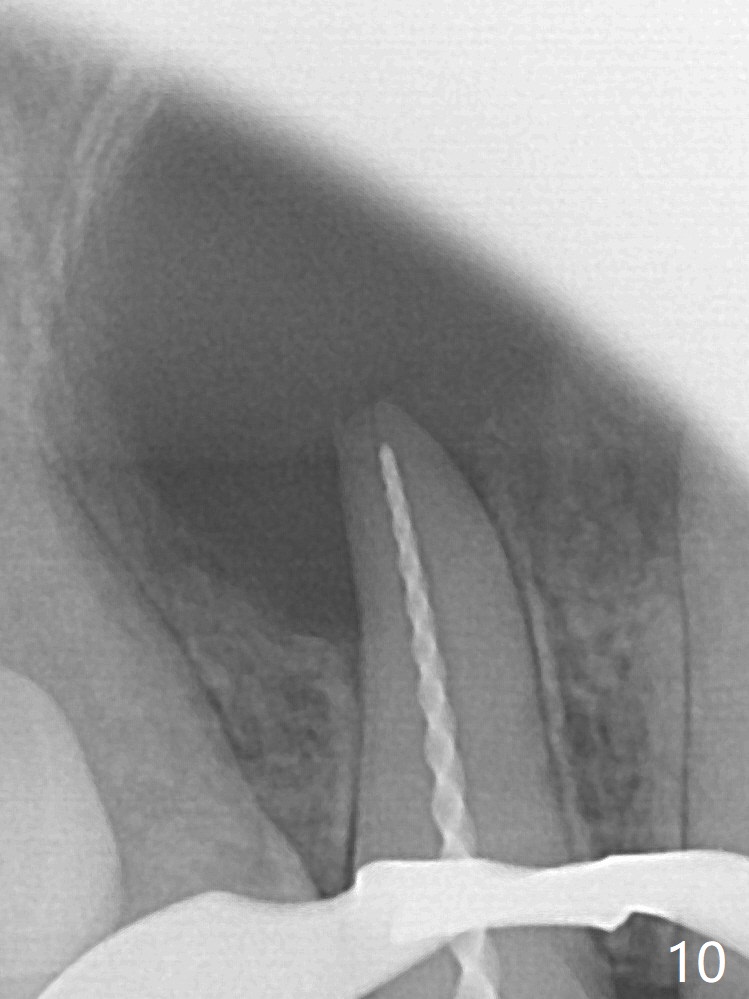

A 47-year-old woman (dental phobic) presented to clinic 9.5 years ago with periapical radiolucency (PARL) at #7 and 9 (Fig.1). RCT was done at #9 because of fistula and symptom 6 months later (Fig.2). While PARL increases at #7 without symptom, that at #9 disappears 8.5 years postop. Three months later, the patient returns for #7 RCT because of the abscesses (Fig.4 *) and pain. Intraop PA is taken with a 30/.06 rotary file in the canal with 19 mm working length (Fig.5). After use of #15 hand file for 20 mm, Ca(OH)2 paste is applied in the canal. When the rubber dam is removed, the abscesses enlarge (Fig.6), which may be related to sodium hypochlorite leakage. A dental explorer is used to try to find a bony opening to the large PARL without success (Fig.7). A postop PA reveals the leakage of Ca(OH)2 paste (Fig.8). Review of the preop PA (Fig.3,9) and intraop PAs (Fig.5,10) shows possible apical resorption and open apical foramen, which is the basis for the paste leakage (Fig.8,11). Careful analysis (with magnification and room light off) of pre- and intra-op PAs should be able to avoid use of #15 hand file out of apical constriction and the complication. The abscess has receded 1 month later (Fig.12). The paste has been resorbed 1 month later (Fig.13). A 30/.06 Gutta Percha is inserted at 18.5 mm (Fig.14 vs. 30/.06 file at 19 mm, 15 file at 20 mm last visit). Fig.15 is the final PA after closure of the access with composite (Fig.15).